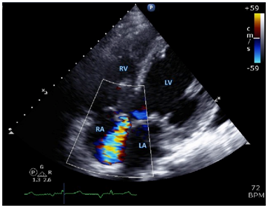

Figure 1 Transthoracic Echocardiographic Study. In the apical four-chamber view obtained at mid – systole with color Doppler Jet flowing from the aortic valve to the right atrium.

RA denotes right atrium, RV right ventricle, LA left atrium and LV left ventricle. RA denotes right atrium, RV right ventricle, LA left atrium, RCC right coronary cusp, LCC left coronary cusp, N non-coronary cusp and asterisk aneurysm.